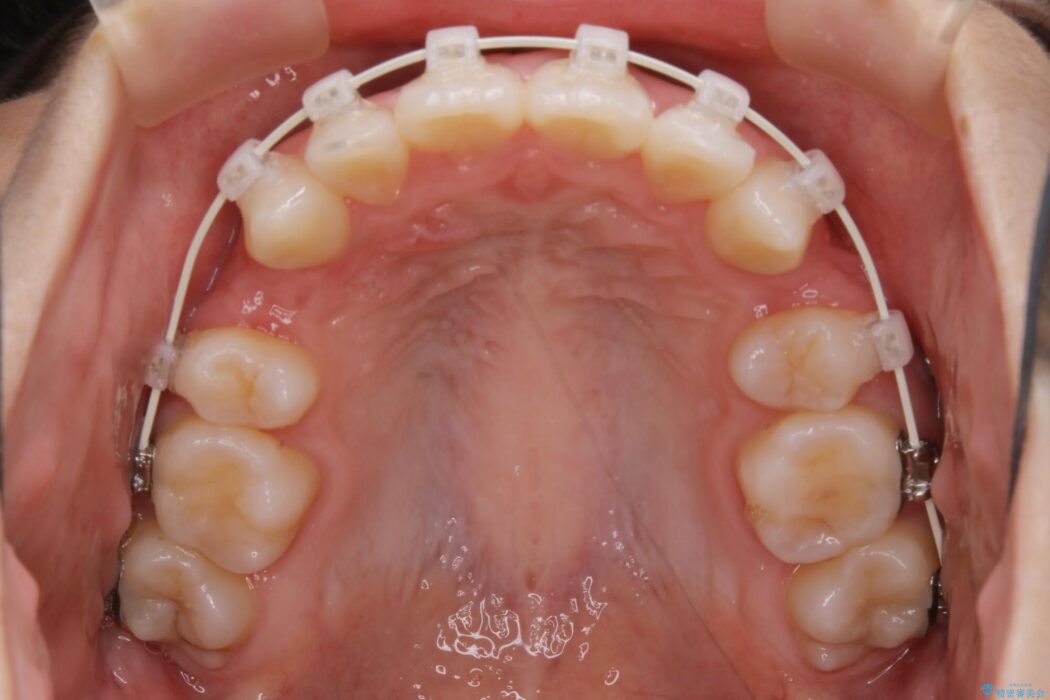

よって本症例では抜歯により歯の本数を減らすことにより整えるスペースを確保してワイヤー装置にて歯列矯正を行うこととしました。

抜歯を行うことによりスペースを確保し、小さい骨幅でも歯並びを整えることができます。